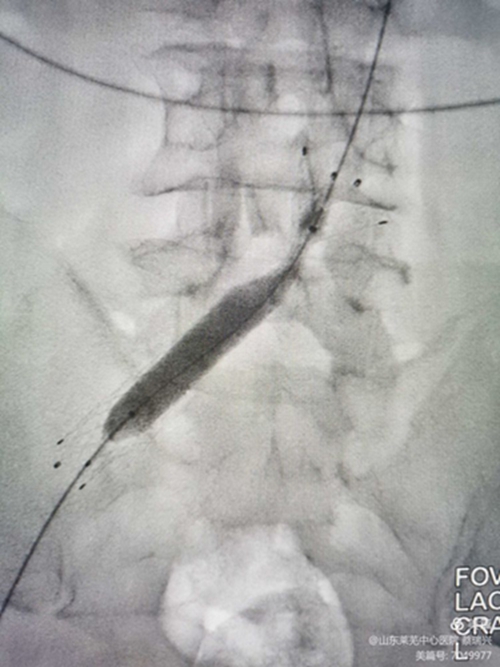

釋放支架,行后擴(kuò)張,球囊有“腰征",且很窄,考慮閉塞段像"噗"一樣。

噗征